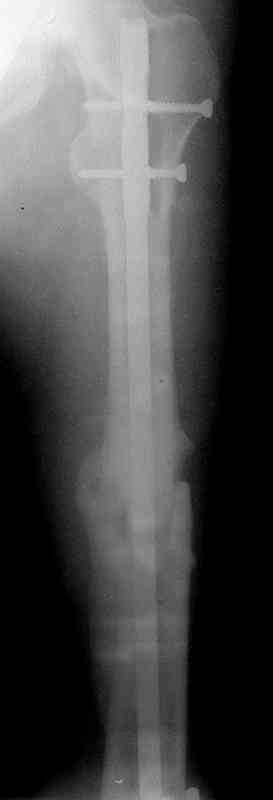

Больной А., 28 лет, поступил в НИИ им. Н.В. Склифосовского 22.12.99 после падения на улице. Жалобы на боли в области левого тазобедренного сустава и левом бедре. Из анамнеза следовало, что 20.06 во время прыжка с парашютом у него возник закрытый оскольчатый перелом средней трети левой бедренной кости со смещением отломков, по поводу чего в одной из ЦРБ Московской области через 3 дня после травмы был произведен открытый интрамедуллярный остеосинтез штифтом типа Кюнчера.

Послеоперационное течение было гладким. Больной ходил при помощи костылей с дозированной нагрузкой на оперированную конечность.При осмотре в НИИ им. Н.В. Склифосовского через 6 месяцев после травмы:

левое бедро и левый коленный сустав несколько увеличены в объеме, отечны, пальпаторно определяется болезненность в средней трети бедра;

по его наружной поверхности послеоперационный рубец - рана зажила первичным натяжением. При измерении длины бедер обнаружено укорочение левого бедра на 4,5 см. На рентгенограммах этого бедра: ось конечности правильная, отмечается захождение основных костных фрагментов по длине, проксимальный конец штифта выступает слишком медиально и высоко относительно большого вертела, периостальная мозоль незначительна.22.12 - через 6 месяцев после операции, произведенной в ЦРБ, нами по поводу замедленно консолидирующего перелома левой бедренной кости с ее абсолютным укорочением под наркозом произведена операция: удаление штифта, закрытый блокирующий интрамедуллярный остеосинтез перелома левого бедра штифтом без рассверливания (UFN) длиной 40 см, диаметром 10 мм с блокированием только проксимальных отверстий (динамический остеосинтез). Наложен аппарат Илизарова на 4 полукольцах с целью удлинения укороченного бедра. Послеоперационное течение без особенностей. Ежедневно осуществляли дистракцию отломков на 1 мм. Через 3 недели после операции больной выпи-сан на амбулаторное лечение с продолжением дистракции отломков. В течение 1,5

месяцев дистракции укорочение левого бедра удалось полностью устранить. 22.02.00, т.е. через 2 месяца после повторного остеосинтеза, больному произведено дистальное блокирование штифта двумя винтами и демонтирован аппарат Илизарова. В течение 2 недель после операции больной ходил с помощью костылей, потом 2 недели с тростью. Опороспособность и функция оперированной конечности полностью восстановились через 4 недели после операции.

Фиксаторы удалены через 12 месяцев после операции, выполненной по поводу замедленной консолидации перелома бедра с его укорочением.